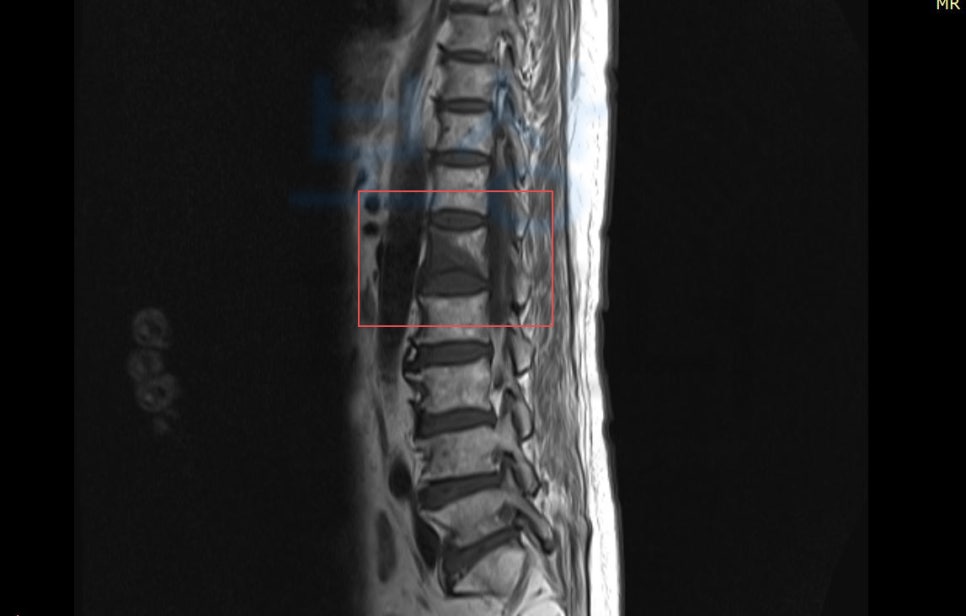

위 사고로 이@@님은 극심한 허리 통증을 호소했고 정밀 검사 상 나온 진단명은

L1 부위의 골절 s32020

경추 염좌, 요추 염좌 진단을 받으셨습니다.

위 사고로 이@@님은 최소 6주간의 요양 및 허리보조기 착용이 필요하셨지요.

**척추에 경미한 장해 15%**에 해당하셨습니다. 저희는 위 진단서를 기초로 손해사정서 및 관련 증빙서류를 검토 및 준비하여 보험사에 청구하였습니다. 물론 보험사에서는 심사를 진행하여 내부자문, 의료자문등을 거쳐 약 2달간의 분쟁이 오갔지만, 결국!